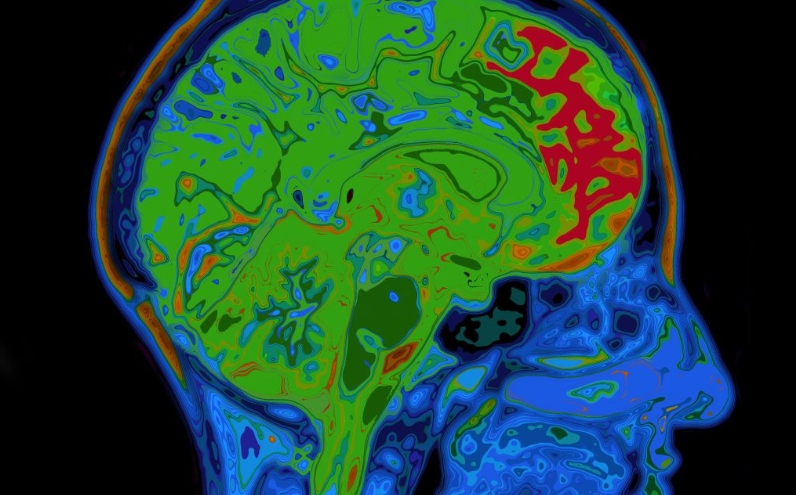

Araştırmacılar, çalışmanın başında hiçbirinde bilişsel gerileme olmayan bir grup gönüllüyü inceledi. Tüm katılımcılardan dışkı, kan ve beyin omurilik sıvısı örnekleri verildi, beyin taramaları yapıldı ve çalışma sırasında bir yiyecek günlüğü tutuldu.

Beyin taramaları ve beyin omurilik sıvısı örnekleri aracılığıyla amiloid beta ve tau oluşumunun işaretlerini arayan araştırmacılar, 164 katılımcının yaklaşık üçte birinin erken Alzheimer hastalığının belirtilerini gösterdiğini buldu.